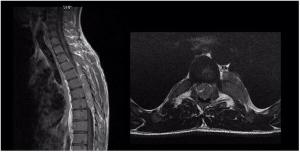

Image IQ: 25-year-old, Progressive Lower Extremity Weakness

25-year-old man presents with progressive lower extremity weakness.